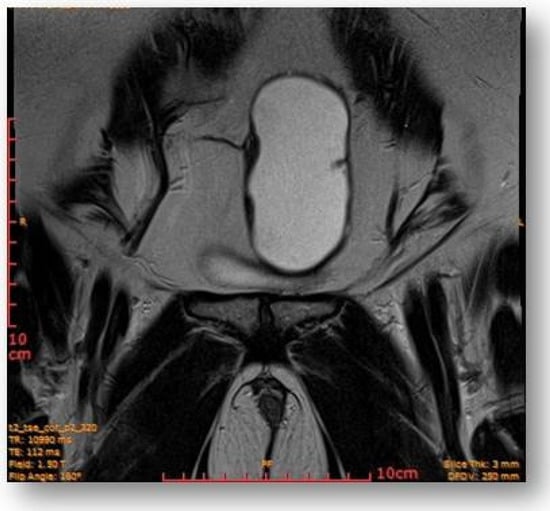

The rectal ampulla did not show suspicious tumor masses. Several infracentimetric pelvic lymph nodes, without specific character, were noted, as well as a minimal plate of intrapelvic fluid with a millimeter thickness. No notable collections in the pelvic recesses. No suspicious focal bone lesions were evident in the pelvis on the acquired images. Diastasis of the rectus abdominis muscles in the pelvic region (distance of about 30–35 mm) could be observed (Figure 7 and Figure 8).

Ovoid cystic lesion proteinaceous fluid content and mildly irregular wall thickness up to ~4–5 mm.

Ovoid cystic lesion in the left part of the uterus.